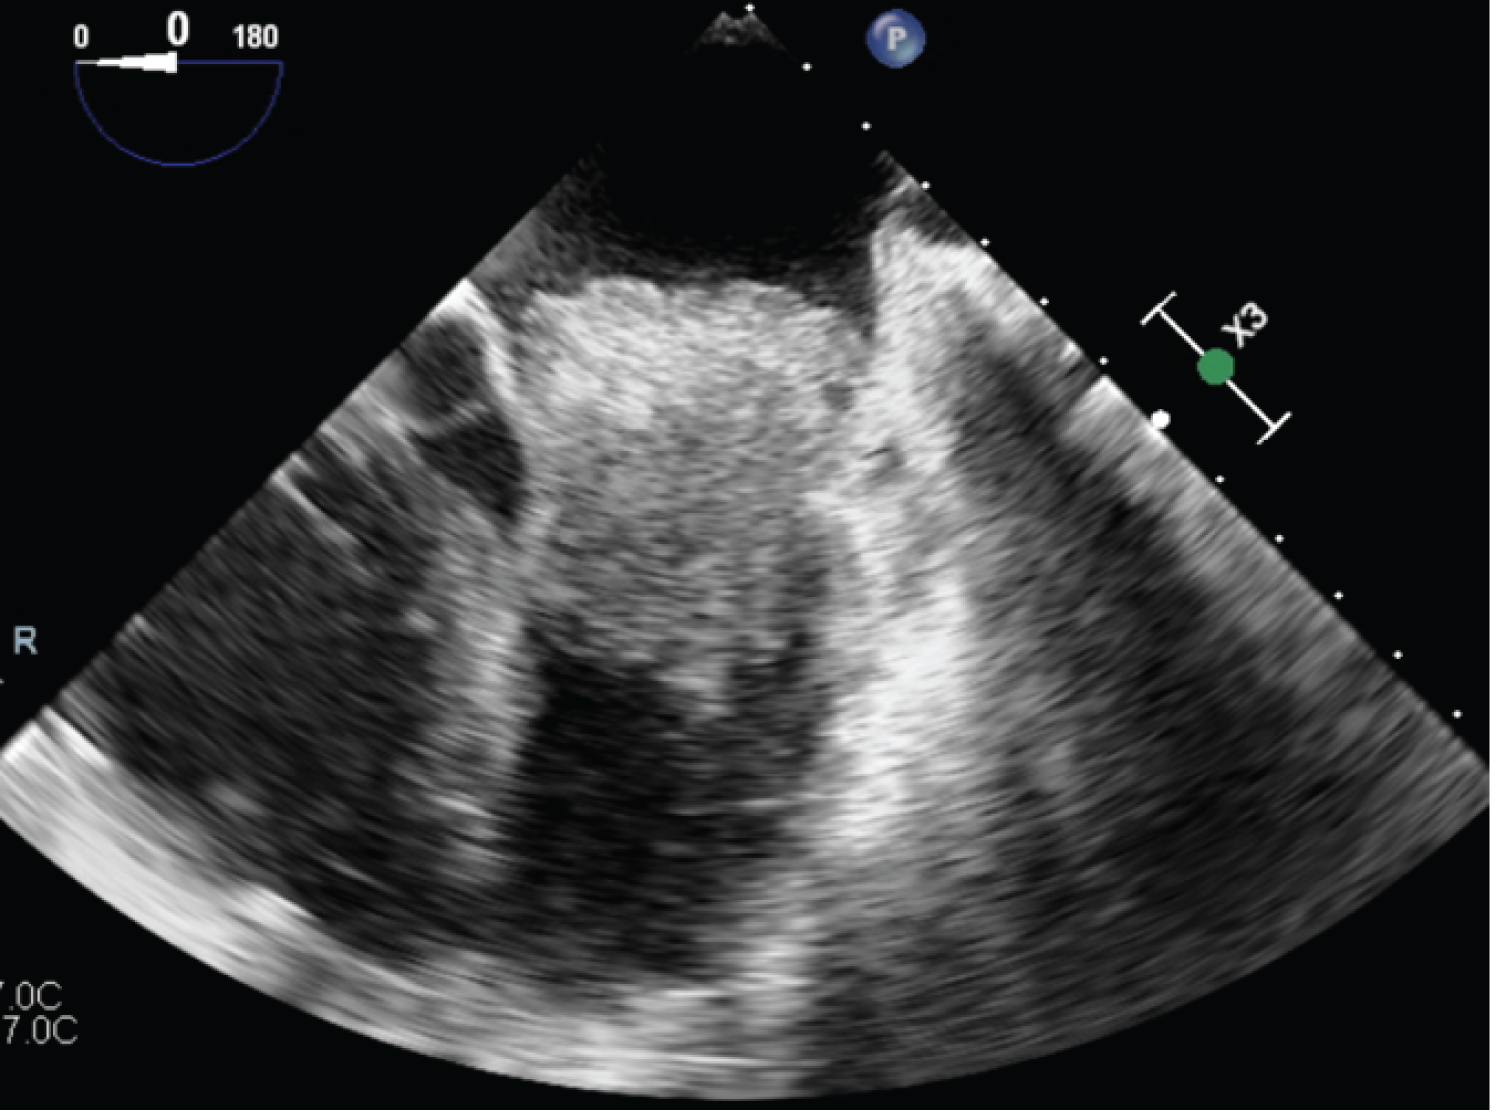

Figure 3: Left atrial mass approximately 2.5 cm × 1.5 cm located in or where left atrial appendage should be noted on TEE 5/4/23. View Figure 3